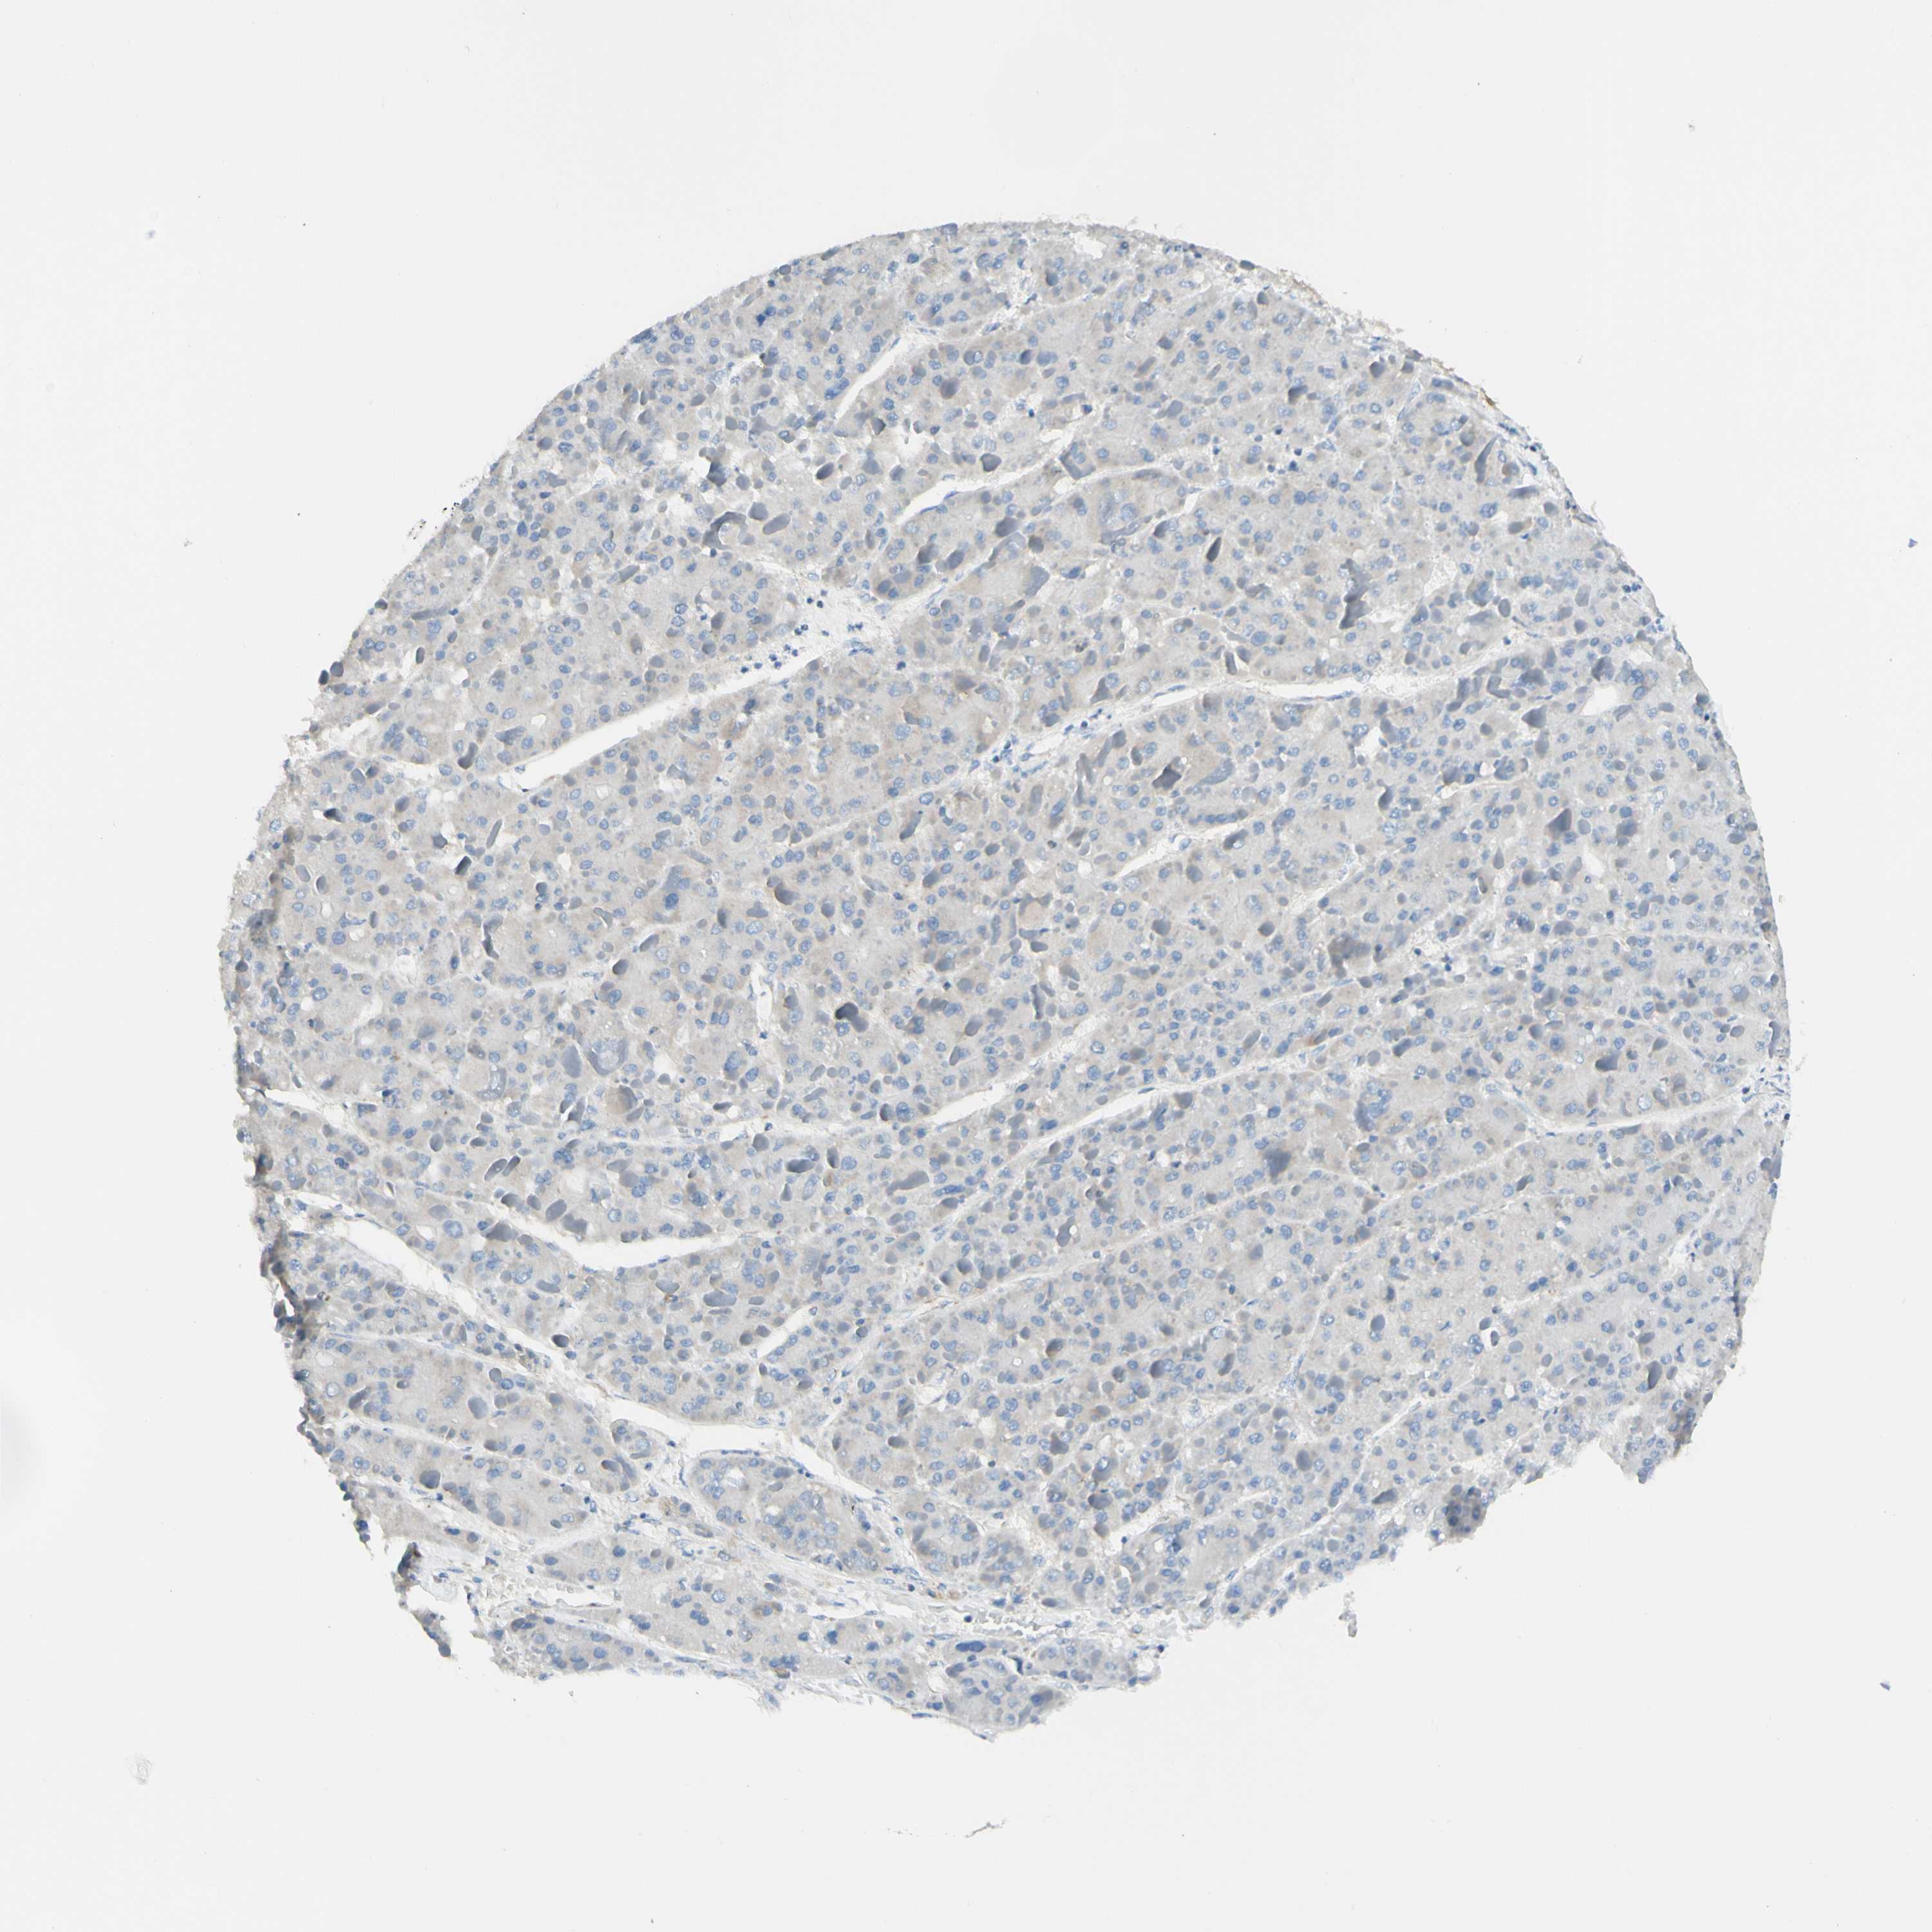

LIVER CANCER - Protein expressioni

A mouse-over function shows sample information and annotation data. Click on an image to view it in a full screen mode. Samples can be filtered based on level of antibody staining by selecting one or several of the following categories: high, medium, low and not detected. The assay and annotation is described here.

Antibody stainingi

Antibody staining in the annotated cell types in the current human tissue is reported as not detected, low, medium, or high, based on conventional immunohistochemistry profiling in selected tissues. This score is based on the combination of the staining intensity and fraction of stained cells.

Each image is clickable and will lead to virtual microscopy that enables deeper exploration of all samples and also displays staining intensity scores, fraction scores and subcellular localization as well as patient and tissue information for each sample.

Antibody HPA011036

Antibody HPA011057

Staining

High

Medium

Low

Not detected

Intensity

Strong

Moderate

Weak

Negative

Quantity

>75%

75%-25%

<25%

None

Location

Nuclear

Cytoplasmic/membranous

Cytoplasmic/membranous,nuclear

Cholangiocarcinoma

Carcinoma, Hepatocellular, NOS